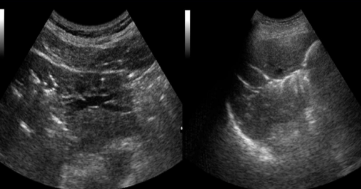

Identify this image.

Cirrhosis